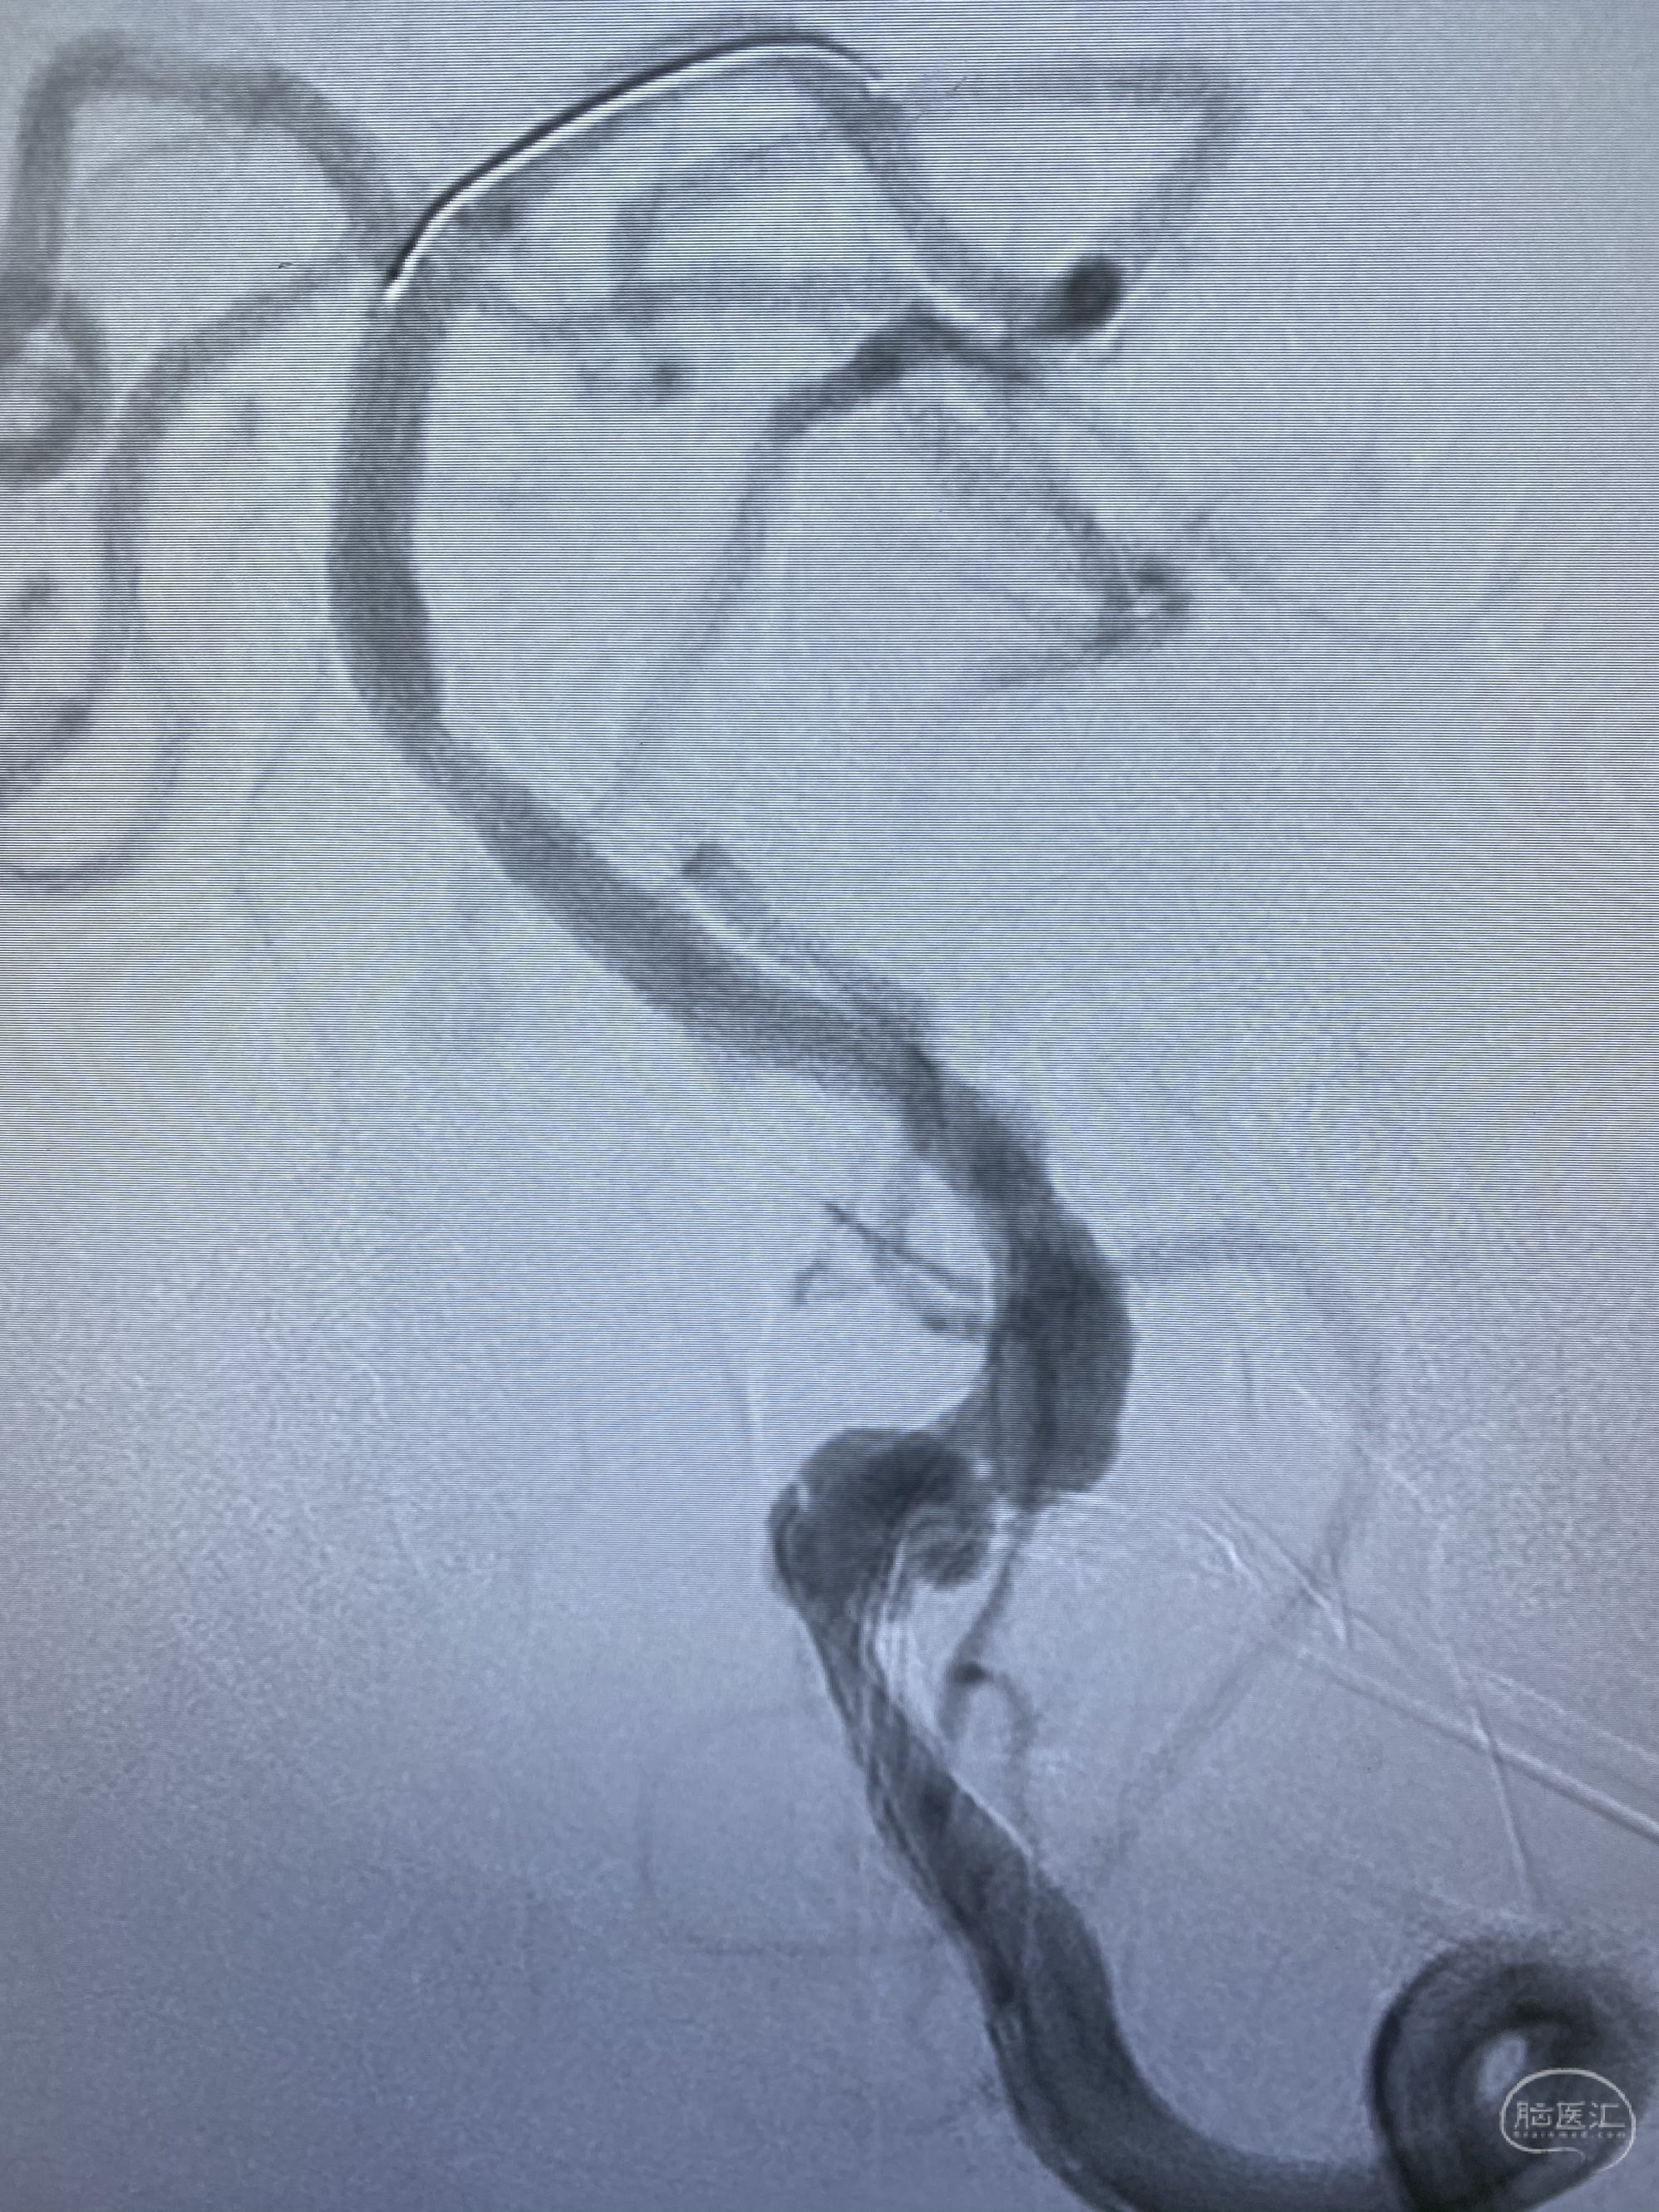

今日手术,TJG,M62Y,一期左侧颈动脉狭窄支架植入,二期椎动脉V4段多发夹层动脉瘤伴狭窄,常规支架辅助栓塞方法复杂又危险,血流导向装置植入快捷又安全。南阳市中心医院神经内科脑血管病介入团队pipeline flexFD植入两人导师资格。

椎动脉颅内段多发夹层动脉瘤伴载瘤动脉狭窄pipeline flex植入

今日手术,TJG,M62Y,一期左侧颈动脉狭窄支架植入,二期椎动脉V4段多发夹层动脉瘤伴狭窄,常规支架辅助栓塞方法复杂又危险,血流导向装置植入快捷又安全。南阳市中心医院神经内科脑血管病介入团队pipeline flexFD植入两人导师资格。